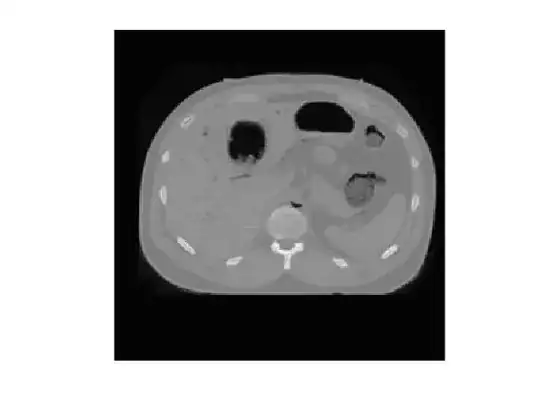

I have following picture

which I extract the contour from. The contour looks like following

I am wondering, for any pixel in the image, how do I determine if it is inside the contour or not? Say "inside" here means any pixel in the body.